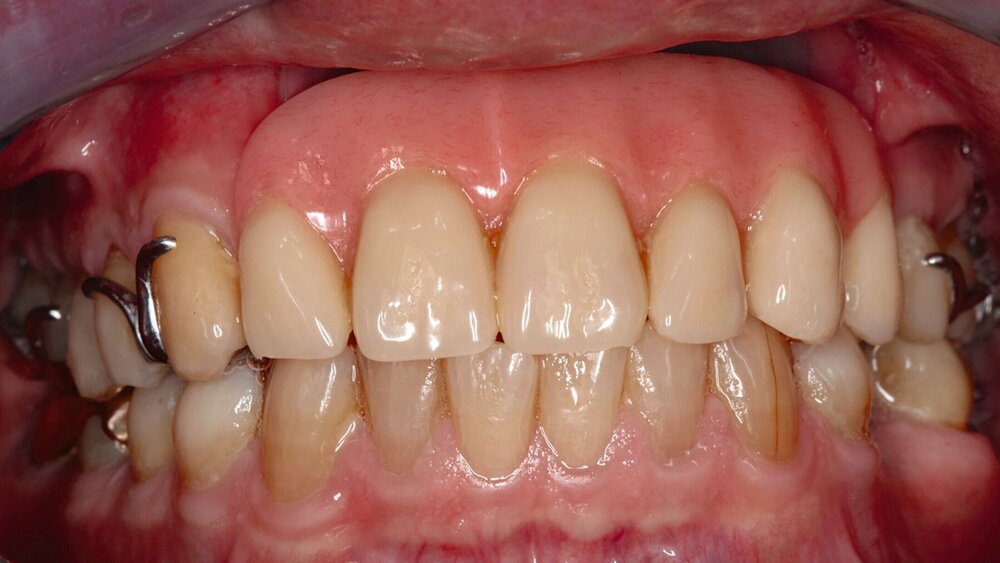

Ein Silikon-Obturator (Abbildung 1) wird über „unter-sich-gehende“ Bereiche im Defekt verankert, kann hohl oder massiv gestaltet sein und sollte im Mund über einen fein auslaufenden Rand (Federrand) am restlichen Weichgewebe enden. Durch diesen feinen Rand ist die Abdichtung zur Nase wie mit einem Saugstopfen sehr gut. Bei fehlendem Vestibulum ist ein fein auslaufender Rand technisch nicht möglich, weshalb durch einen Silikon-Obturator hier nur in seltenen Fällen ein zufriedenstellender Halt erreicht wird. Optimalerweise sollte der Silikon-Obturator täglich vom Patienten entfernt und gereinigt werden können, um die Ansiedlung von Pilzen zu vermeiden.

Bei einer Obturator-Prothese (Abbildung 2) erfolgt der Defektverschluss mittels hartem Acrylat-Prothesenkunststoff. Sie kann im Zenit offen oder geschlossen gestaltet sein. Der Halt wird über Klammern, Teleskope oder eine implantatgetragene Verankerung erzielt. Bei vollständiger Zahnlosigkeit ist eine Obturator-Prothese nicht zu empfehlen, da der gewöhnlich genutzte Saugeffekt nicht hergestellt werden kann. Bei zahnlosen Patienten, die keine Implantate erhalten können oder sollen, ist es sogar empfehlenswert, den Defekt nicht zu rekonstruieren, damit Unterschnitte für einen Silikon-Obturator genutzt werden können.